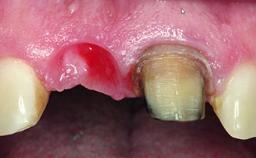

Replacement of a Failing Upper Right Central Incisor, Ridge Preservation and Late Placement of a NC Bone Level Implant

A 30-year-old patient presented at our clinic with a chief complaint of pain in her endodontically treated right maxillary central incisor (tooth 11) with a post-and-core and a fixed single crown. She had a very high lip line, a medium to thin soft-tissue phenotype, and a medium scalloped gingival contour. She also had high esthetic expectations because of her young age and beautiful smile. However, her expectations were realistic and she understood the risks of the treatment. At the initial clinical examination there was a slight mobility of tooth 11; no fistula was observed. The patient also had a single crown on the adjacent tooth 21. Both restorations were old and esthetically deficient. A digital periapical radiograph showed a very small periapical radiolucency, a thick intraradicular post, and no separation between root fragments.

Soft Tissue Anatomy Intact Defective

Bone Volume Horizontally and vertically sufficient Horizontally deficient Deficient vertically or deficient vertically AND horizontally